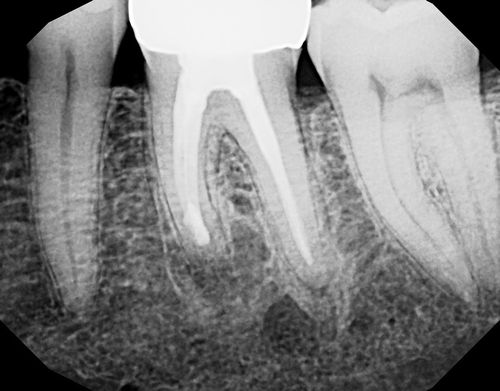

Our highly experienced endodontists understand the importance of accurate diagnosis when it comes to endodontic microsurgery. That’s why we perform a comprehensive examination and assessment, utilizing state-of-the-art X-rays and 3D CBCT imaging technology to identify the root cause of your dental issue. By pinpointing the problem accurately, we can determine if endodontic microsurgery is the most suitable solution for you.

When it comes to endodontic microsurgery, precision is key. Our skilled specialists utilize advanced techniques and high-powered microscopes to access the root tip through a small incision near the affected tooth. With a clear view of the area, we can perform precise and targeted treatment, ensuring the best possible outcome for our patients.